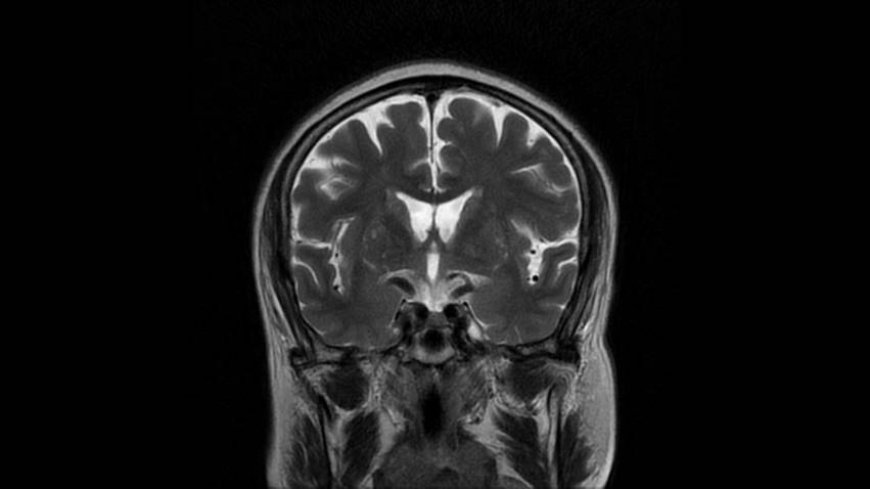

MRI of Brain

Coronal T2